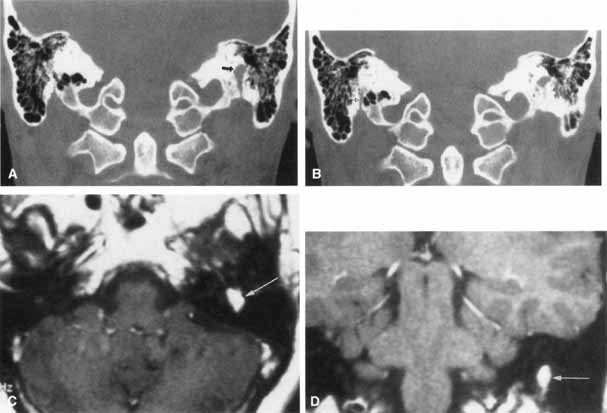

The facial paralysis associated with facial nerve neuromas usually has a gradual onset, but it may be more rapid, simulating idiopathic facial paralysis. Indeed, the pareses may fluctuate or may be associated with hemifacial spasm. In some cases, hearing loss precedes the onset of facial weakness, thereby simulating an acoustic neuroma.93 CT scan typically shows a uniformly enhancing mass in the fallopian canal. T2-weighted MRI images may show a hyperintense mass in the facial canal89 that enhances with gadolinium on T1-weighted images (Fig. 16). The ultimate diagnosis of facial neuroma requires surgical exploration and biopsy. Biopsy usually results in facial paralysis. This possibility should be discussed with the patient before surgery. Facial function recovery after resection of tumor and grafting, although never normal, may include restored tone, symmetry, and weak voluntary movement. The more facial function present before surgery, the better the results with grafting. This observation must be shared with the patient, because he or she might elect to wait until facial function is lost before consenting to surgical removal. When the tumor is located eccentrically, removal is possible with preservation of facial function.94

Fig. 16 Patient with facial neuroma. A. Coronal CT scan demonstrating enlarged stylomastoid foramen and facial nerve mass (arrow). B. Note size of canal in Figure A (black arrow) compared with normal sized canal (open arrow). C. Axial MRI scan showing an enhancing mass of tympanic segment (arrow). D. Coronal gadolinium-enhanced MRI section demonstrating same mass in mastoid segment (arrow).